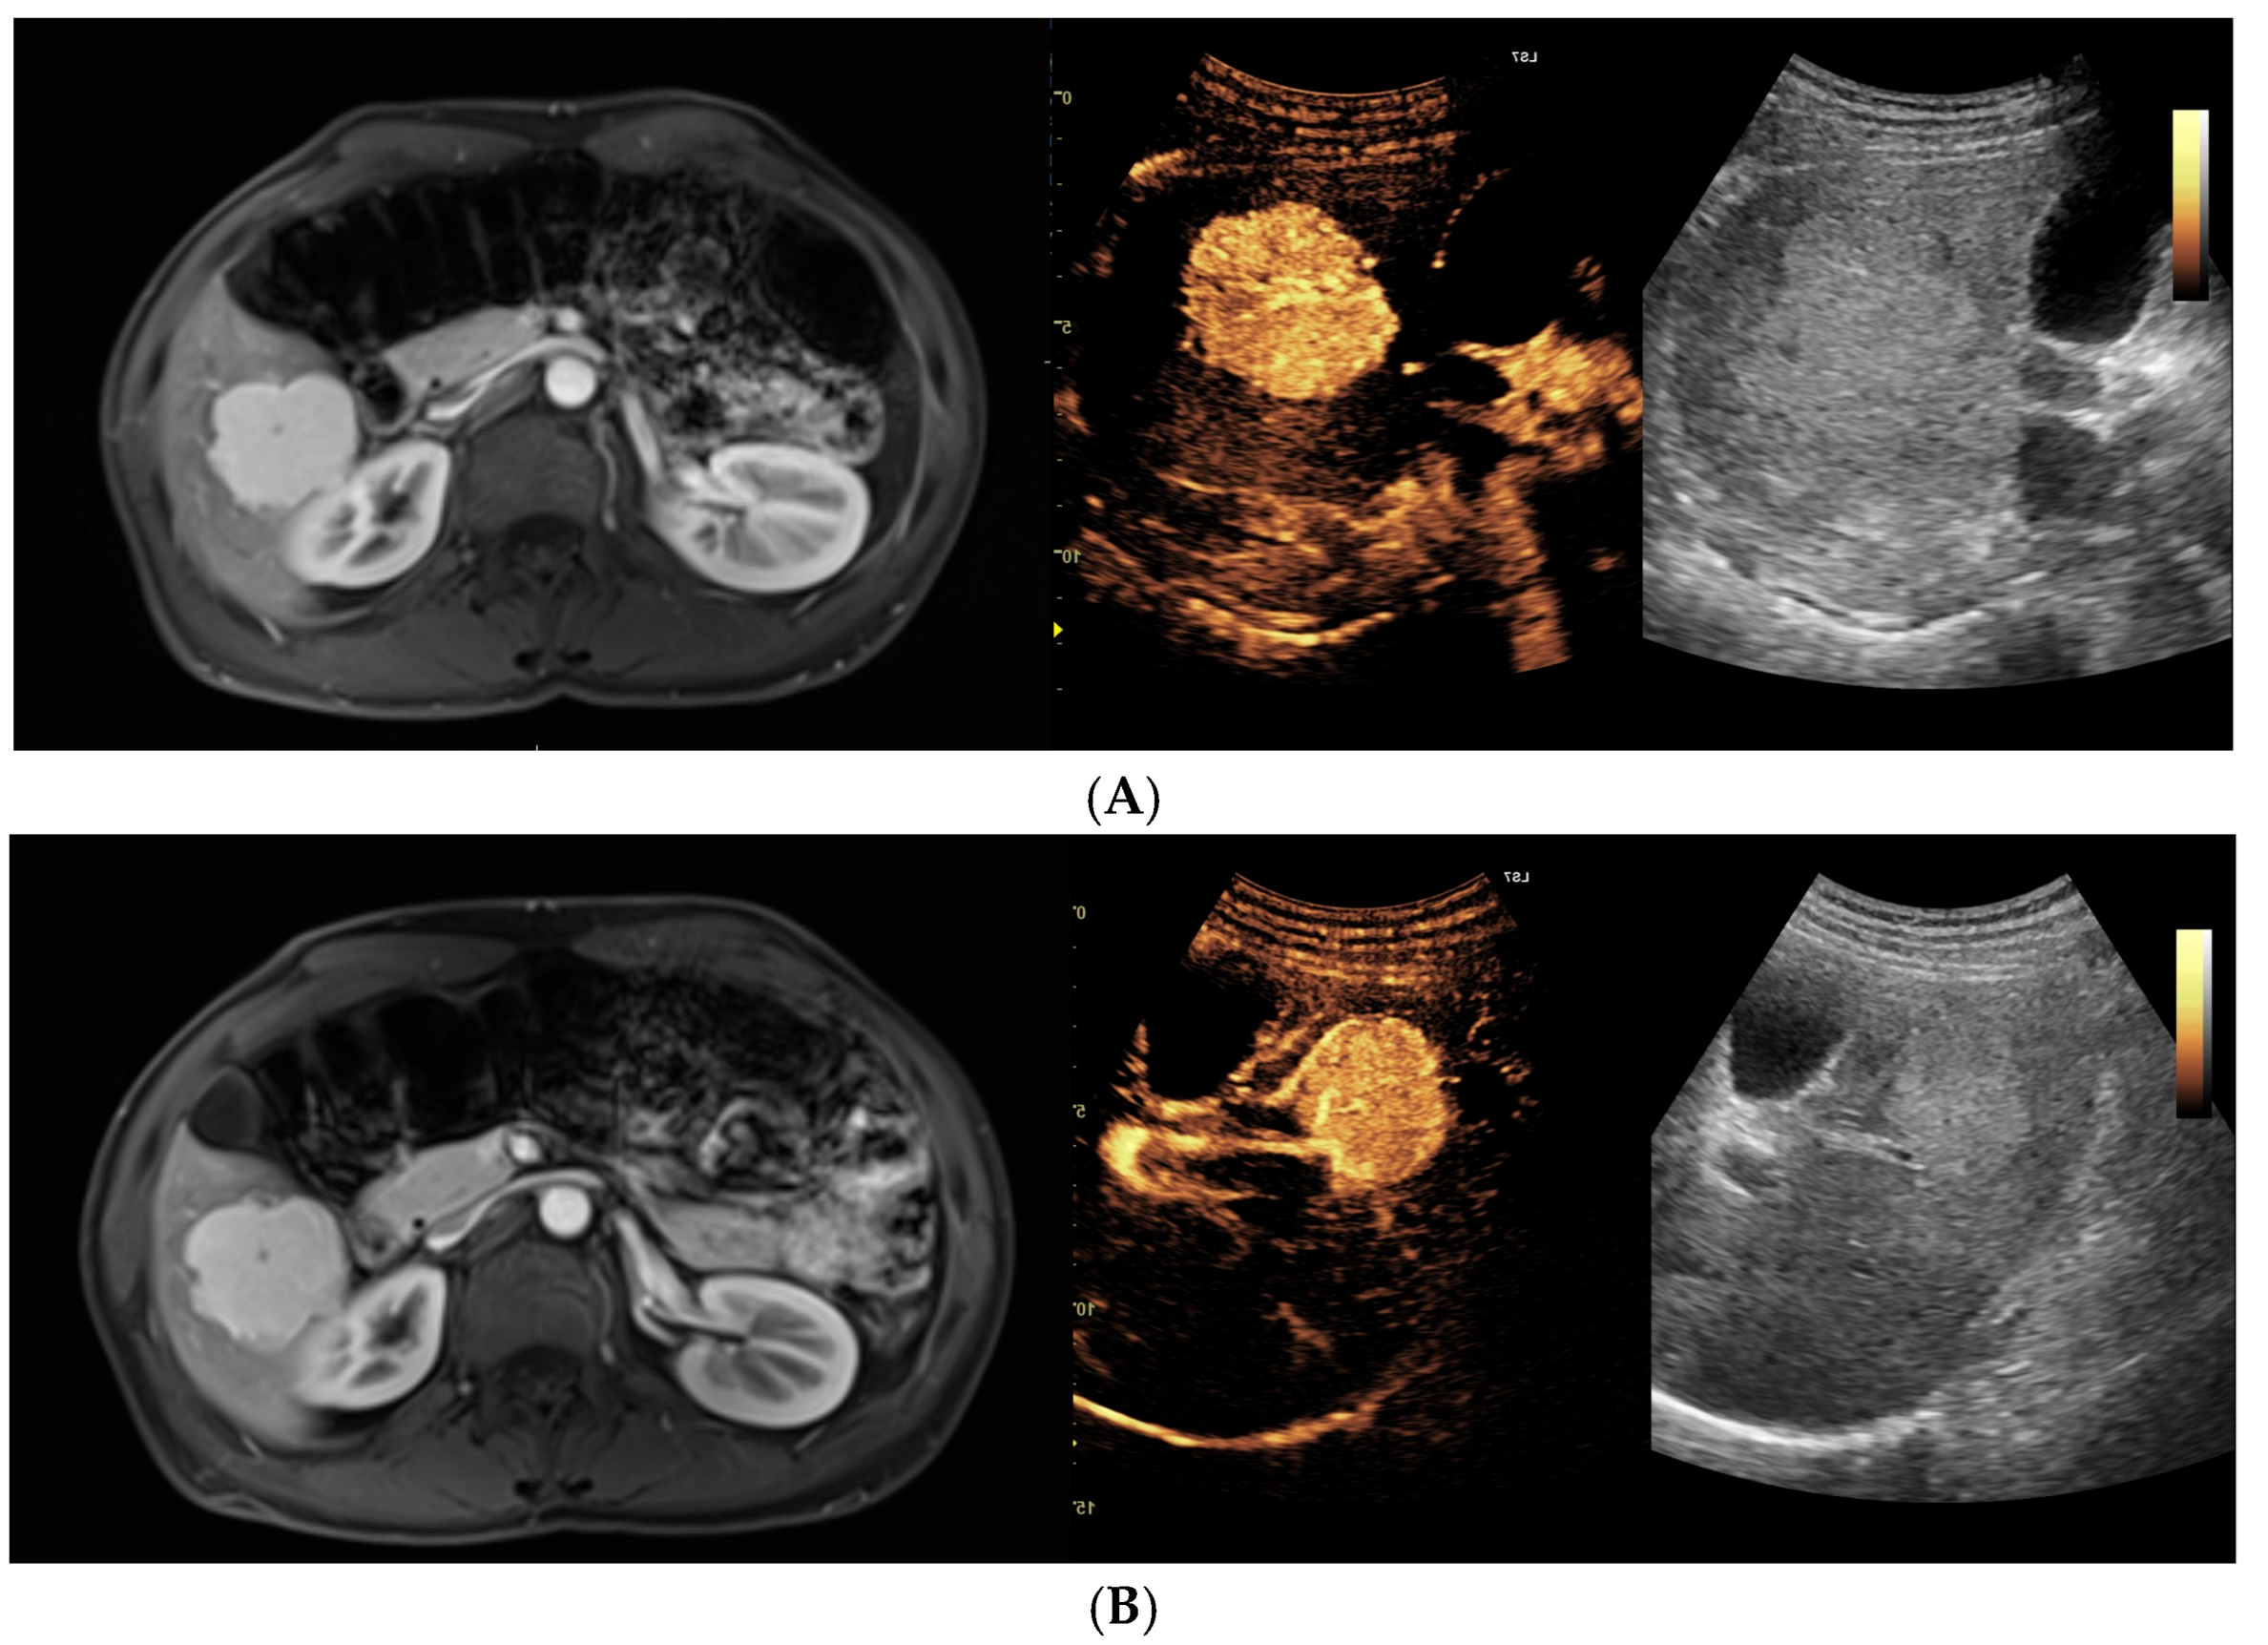

- Dobek, A.; Kobierecki, M.; Wieczorek, P.; Grząsiak, O.; Ciesielski, W.; Fabisiak, A.; Stefańczyk, L. Contrast-enhanced ultrasonography as a method of monitoring focal liver lesions—Initial report. Clin. Exp. Hepatol. 2024, 10, 120–128. [Google Scholar] [CrossRef] [PubMed]

- Dobek, A.; Kobierecki, M.; Ciesielski, W.; Grząsiak, O.; Fabisiak, A.; Stefańczyk, L. Usefulness of Contrast-Enhanced Ultrasound in the Differentiation between Hepatocellular Carcinoma and Benign Liver Lesions. Diagnostics 2023, 13, 2025. [Google Scholar] [CrossRef]